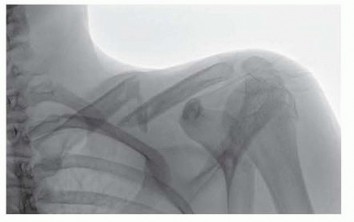

DEFINITION Nonarticular scapular fractures include fractures of the glenoid neck, scapular spine and body, ac…

DEFINITION Displaced, comminuted fractures of the clavicle are at risk for nonunion and malunion 3 , 4 , 6 , …